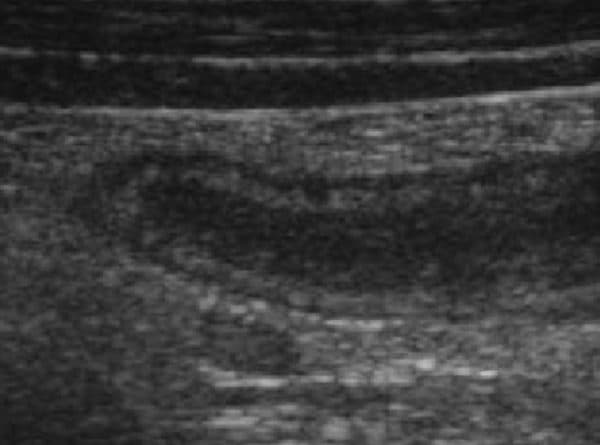

Ruột thừa bình thường sẽ xuất phát từ manh tràng, cấu trúc hình ống và không có nhu động. Theo thứ tự từ ngoài vào trong bao gồm lớp thanh mạc, lớp cơ, lớp dưới niêm mạc, lớp niêm mạc và cuối cùng là lòng ruột thừa. Thành dày khoảng 2mm và có đường kính dưới 6-7mm.

Trường hợp ruột thừa bị viêm trên siêu âm là hình ảnh cấu trúc hình ống, chứa đầy dịch với cấu tạo như ruột, không đè ép được, thành ruột dày, và có đường kính lớn hơn 6-7 mm. Khi dùng đầu dò đè lên có thể phân biệt được một bên quai ruột di chuyển được với một bên ruột thừa viêm cố định.

Hình ảnh ruột thừa sưng to được hiển thị trên siêu âm giúp bác sĩ dễ dàng đánh giá chính xác tình trạng bệnh.